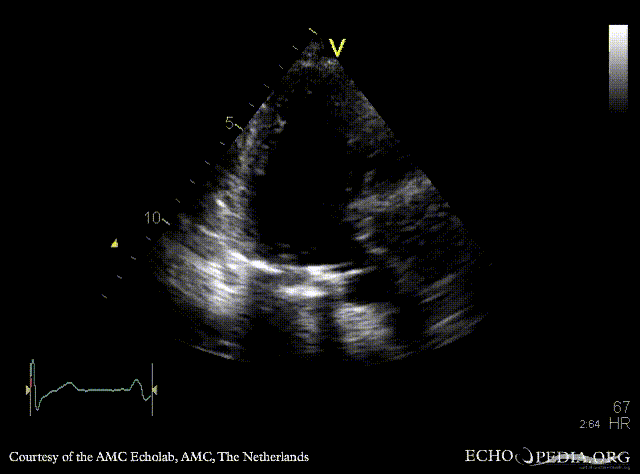

E00598.gif E00599.gif

A4CH A2CH